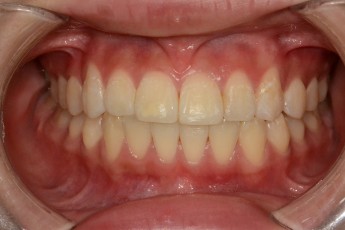

BEFORE & AFTER